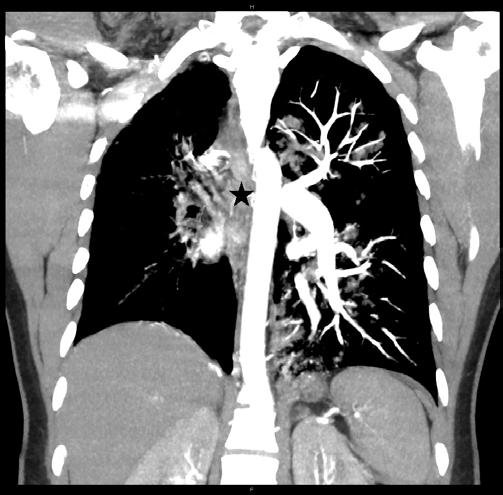

A plain film of the chest was ordered, which was interpreted by radiology as probable left-sided tension pneumothorax (Image 1). However, the treating physician thought that pulmonary edema was more likely based on real-time interpretation of this image along with physical exam findings. Due to an inconsistency between the clinical presentation and imaging report, a contrast-enhanced computed tomography angiography was ordered, which revealed an absent right pulmonary artery and hypoplastic right lung (Images 2, 3).

Image 2. A coronal view of a contrast-enhanced computed tomography angiography revealing an absent right pulmonary artery (star) and hypoplastic right lung. CPC-EM Capsule